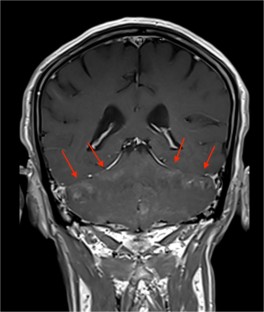

Fig. 1